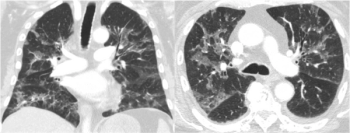

Prostate-specific membrane antigen PET/CT was found to be a suitable replacement for conventional imaging in patients with prostate cancer, providing superior accuracy to the combined findings of CT and bone scanning.